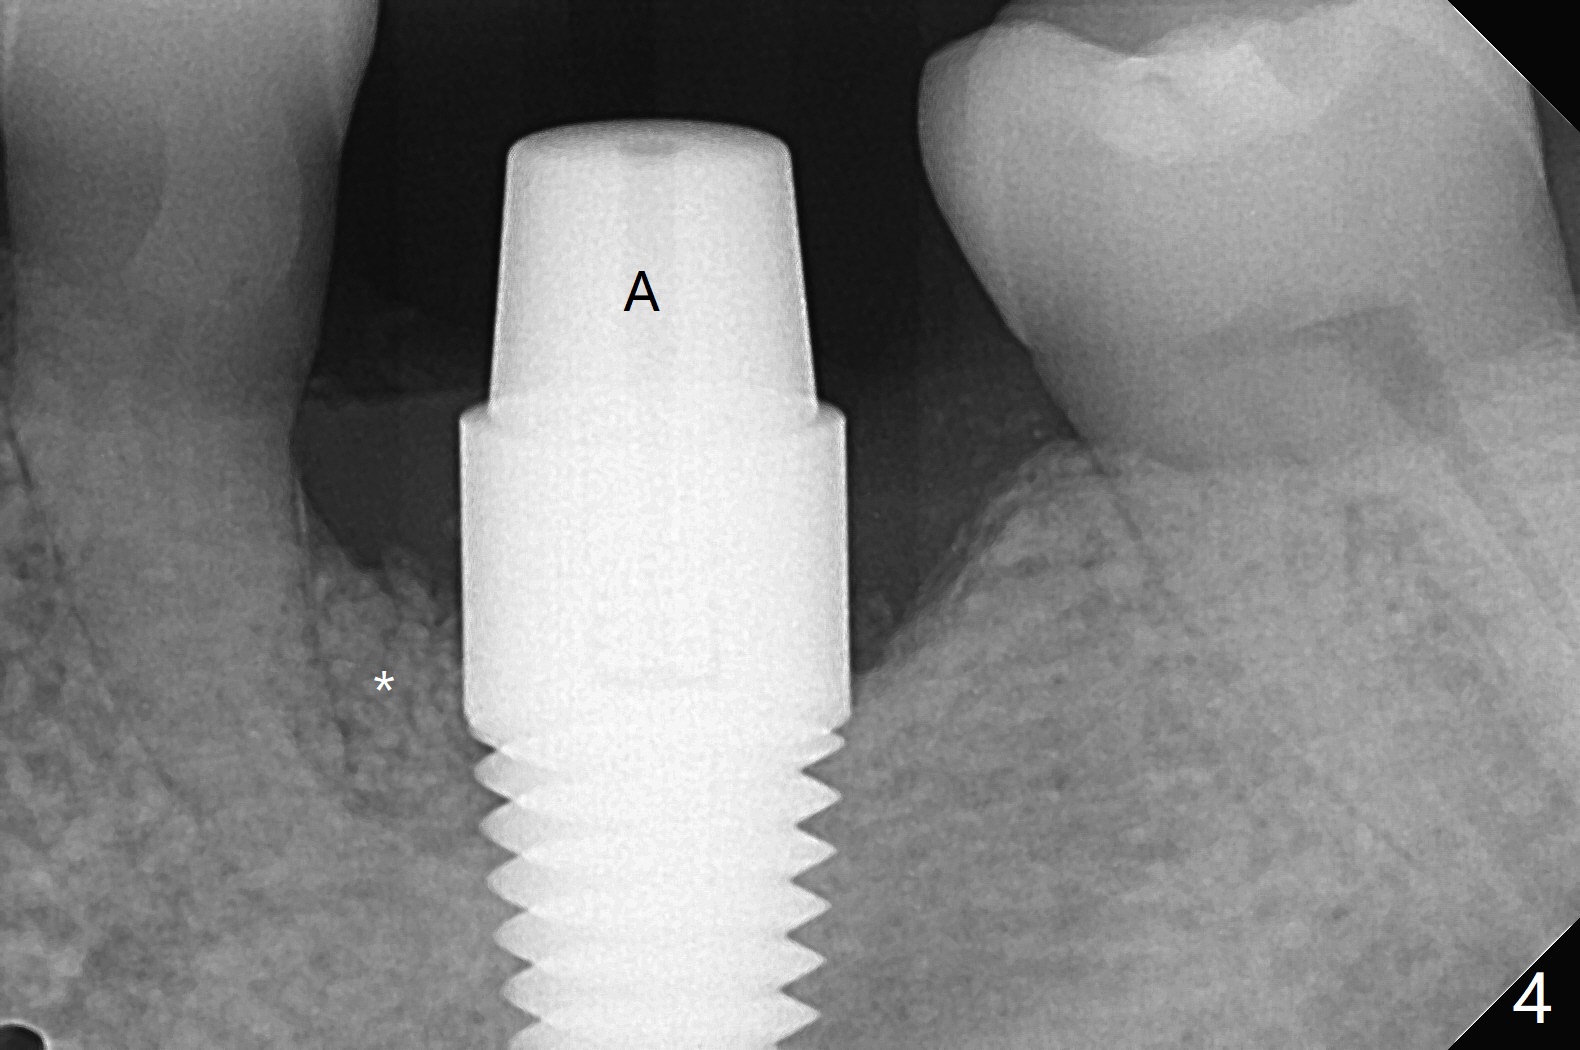

左下6植体周围炎诊断后两周,病人回来做植骨,服用抗菌素一周,炎症有所减轻,但口腔卫生不佳(图一)。软组织水平植体表面菌斑去除后,才切开,清除肉芽组织,钛刷(图二),双氧水擦洗,放置粘性骨粉(图三)和PRF膜,缝合,安置基台(图四:A),有利于牙周敷料固定。术后第二天病人汇报左下唇麻木,不肯用药;第六天回来(图五),麻木造成嘴唇创伤,同意服用Medrol Dosepak。